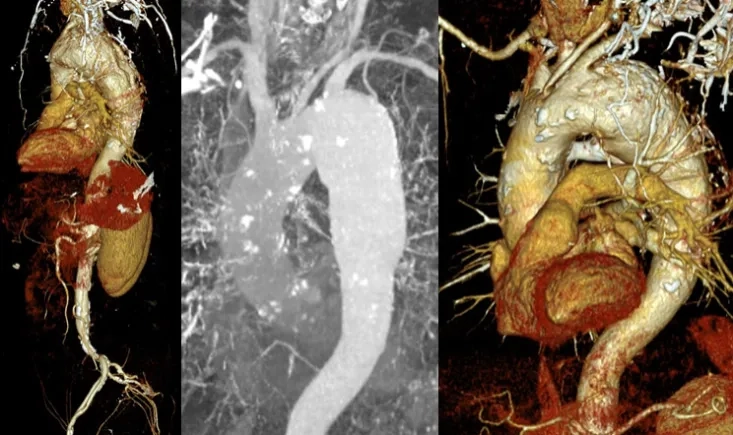

A 73-year-old man with major cardiovascular risk factors presented with acute pain and was diagnosed with a…